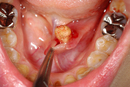

患部の触知・視診結果

小さい結石は黙っていることもありますが、導管の末端近くであれば口腔内から硬いしこりを触れることもあります 。

重度の場合は触診で腺の腫れや圧痛も確認されます。

感染伴う症状(膿・発熱)

長期閉塞が続くと唾液腺炎となり、発熱、赤み、顔面や頸部の腫れ、膿の排出を伴うこともあります 。

視診・触診による初期診断

口腔内・顔面からの**所見(硬いしこり・腺の腫れ・圧痛)**で疑いを持ちます 。